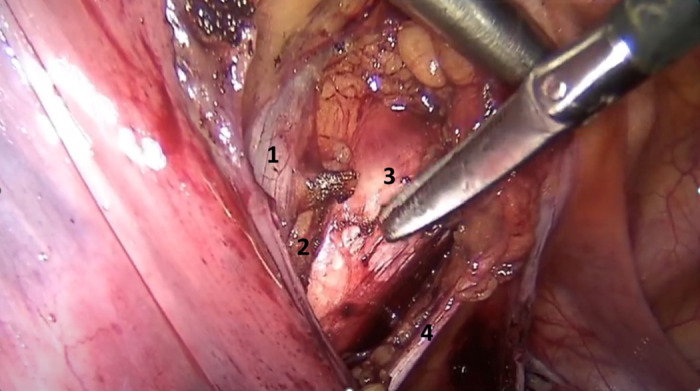

Background: Pelvic organ prolapse (POP) is a common gynaecological condition that can have an adverse impact on women's quality of life. Apical prolapse refers to the descending of the vaginal apex, uterus or cervix. Nowadays, laparoscopic sacropexy (LS) is the gold standard surgical method for the treatment of apical prolapse. However, defecation and urinary problems are often detected in patients who underwent LS. Laparoscopic pectopexy (LP) is a newer procedure for apical prolapse correction that uses the iliopectineal ligaments as fixation point for the surgical mesh.